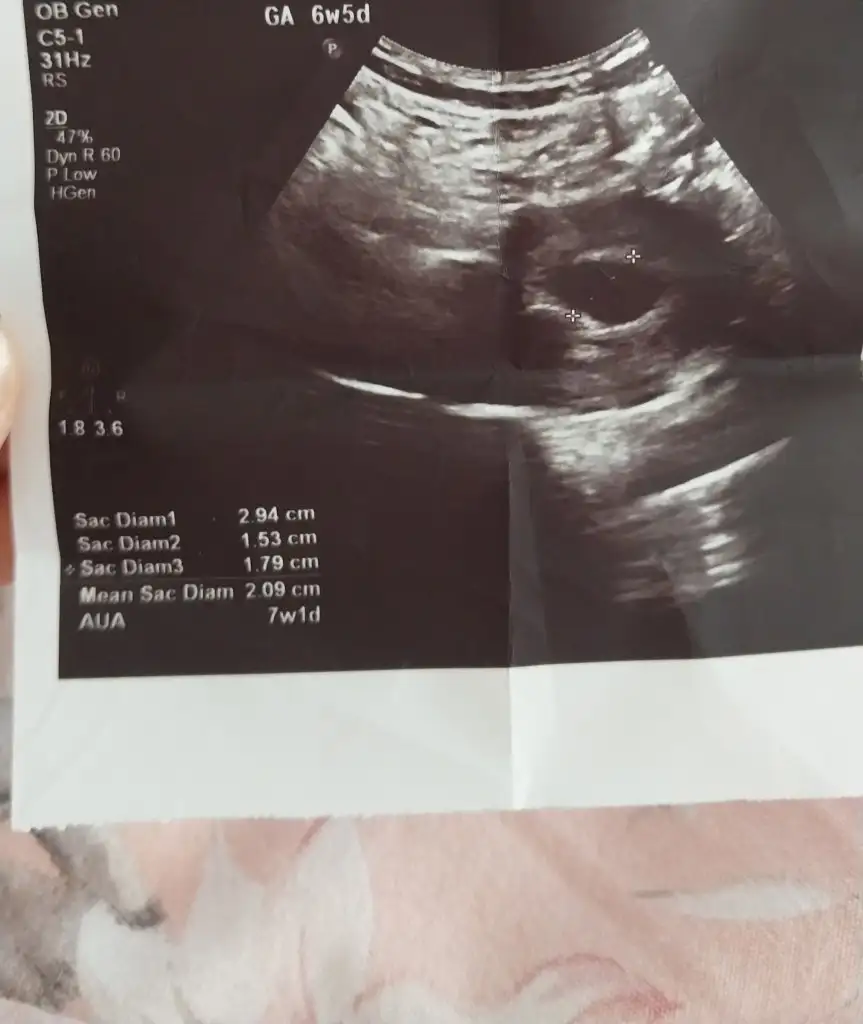

🥰 Buraya kendi ultrason çıktımı bırakıyorum . Çıktıdan, nispeten iyi bir cihaz olduğu anlaşılıyor . Bazı çıktılar çok bulanık , ordan da cihazın eski ya da bozuk olduğu anlaşılıyor. Sen bence farklı bir doktora git . Çünkü 10 gün beklemek için çok uzun . Burda kese görünmedi , bebek görünmedi diyen yorumlar çok fazla . Çoğu da başka doktora gidip bebekleri gördüler canım . Sende git ki için rahatlasın 🌸

Ultrason goruntum bakabilir misiniz kizlad cicekkiz9 cicekkiz9

Canım şimdiye kadar yolk saçın ve bebek görünmesi lazımdı en azından yolk saç görünse bile yeterdi bu duruma doktorlar ne diyor ? Seni üzmek istemem ama benim boş gebeliğim de böyleydi ☹️ umarım ultrason eskidir 🙏

Dr 10 gün sonra netleşir dedi yolk saç ile ilgili bir şey demediler .inşallah canım peki boş gebeliginde beta artışın devam ediyor muydi